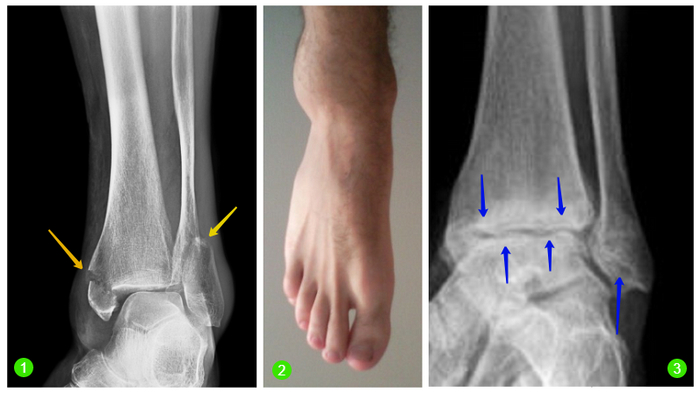

Когда я более-менее пришёл в себя, то заметил что сбоку на голеностопе начинает вздуваться основательный по своим размерам шишак. По глупости своей подумав что это всего лишь вывих, стиснув зубы, я заковылял до остановки. Лишь там, просидев минут десять, я понял что мне несколько хреново... Здраво оценив свои силы, я вызвал скорую помощь и поехал в больницу, где мне поставили диагноз: закрытый перелом со смещением.Почти вот такой)):